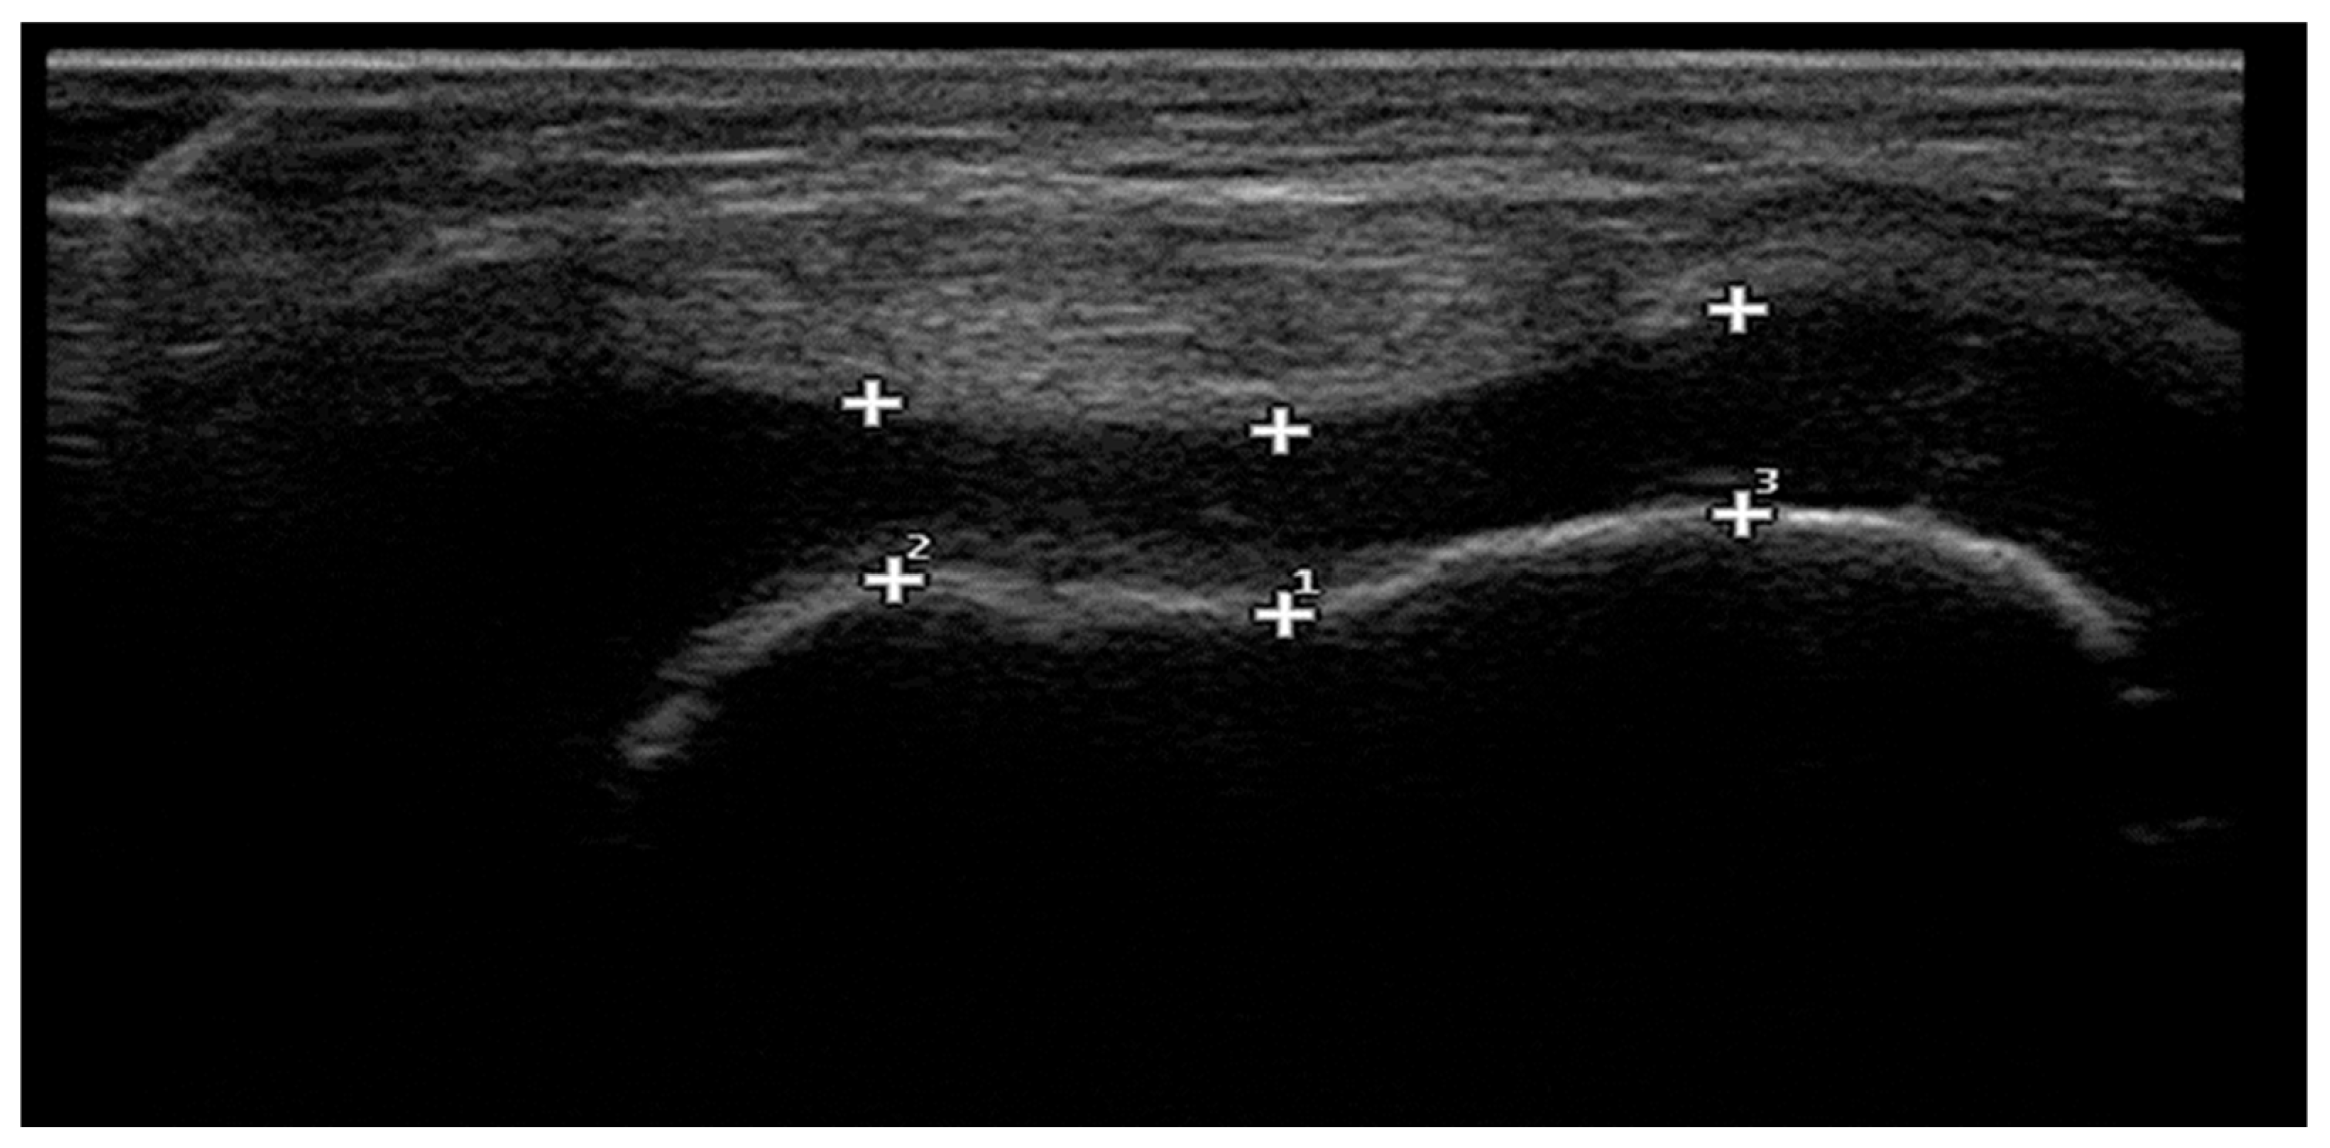

2.6. Ultrasonographic Measurement of Femoral Cartilage Thickness